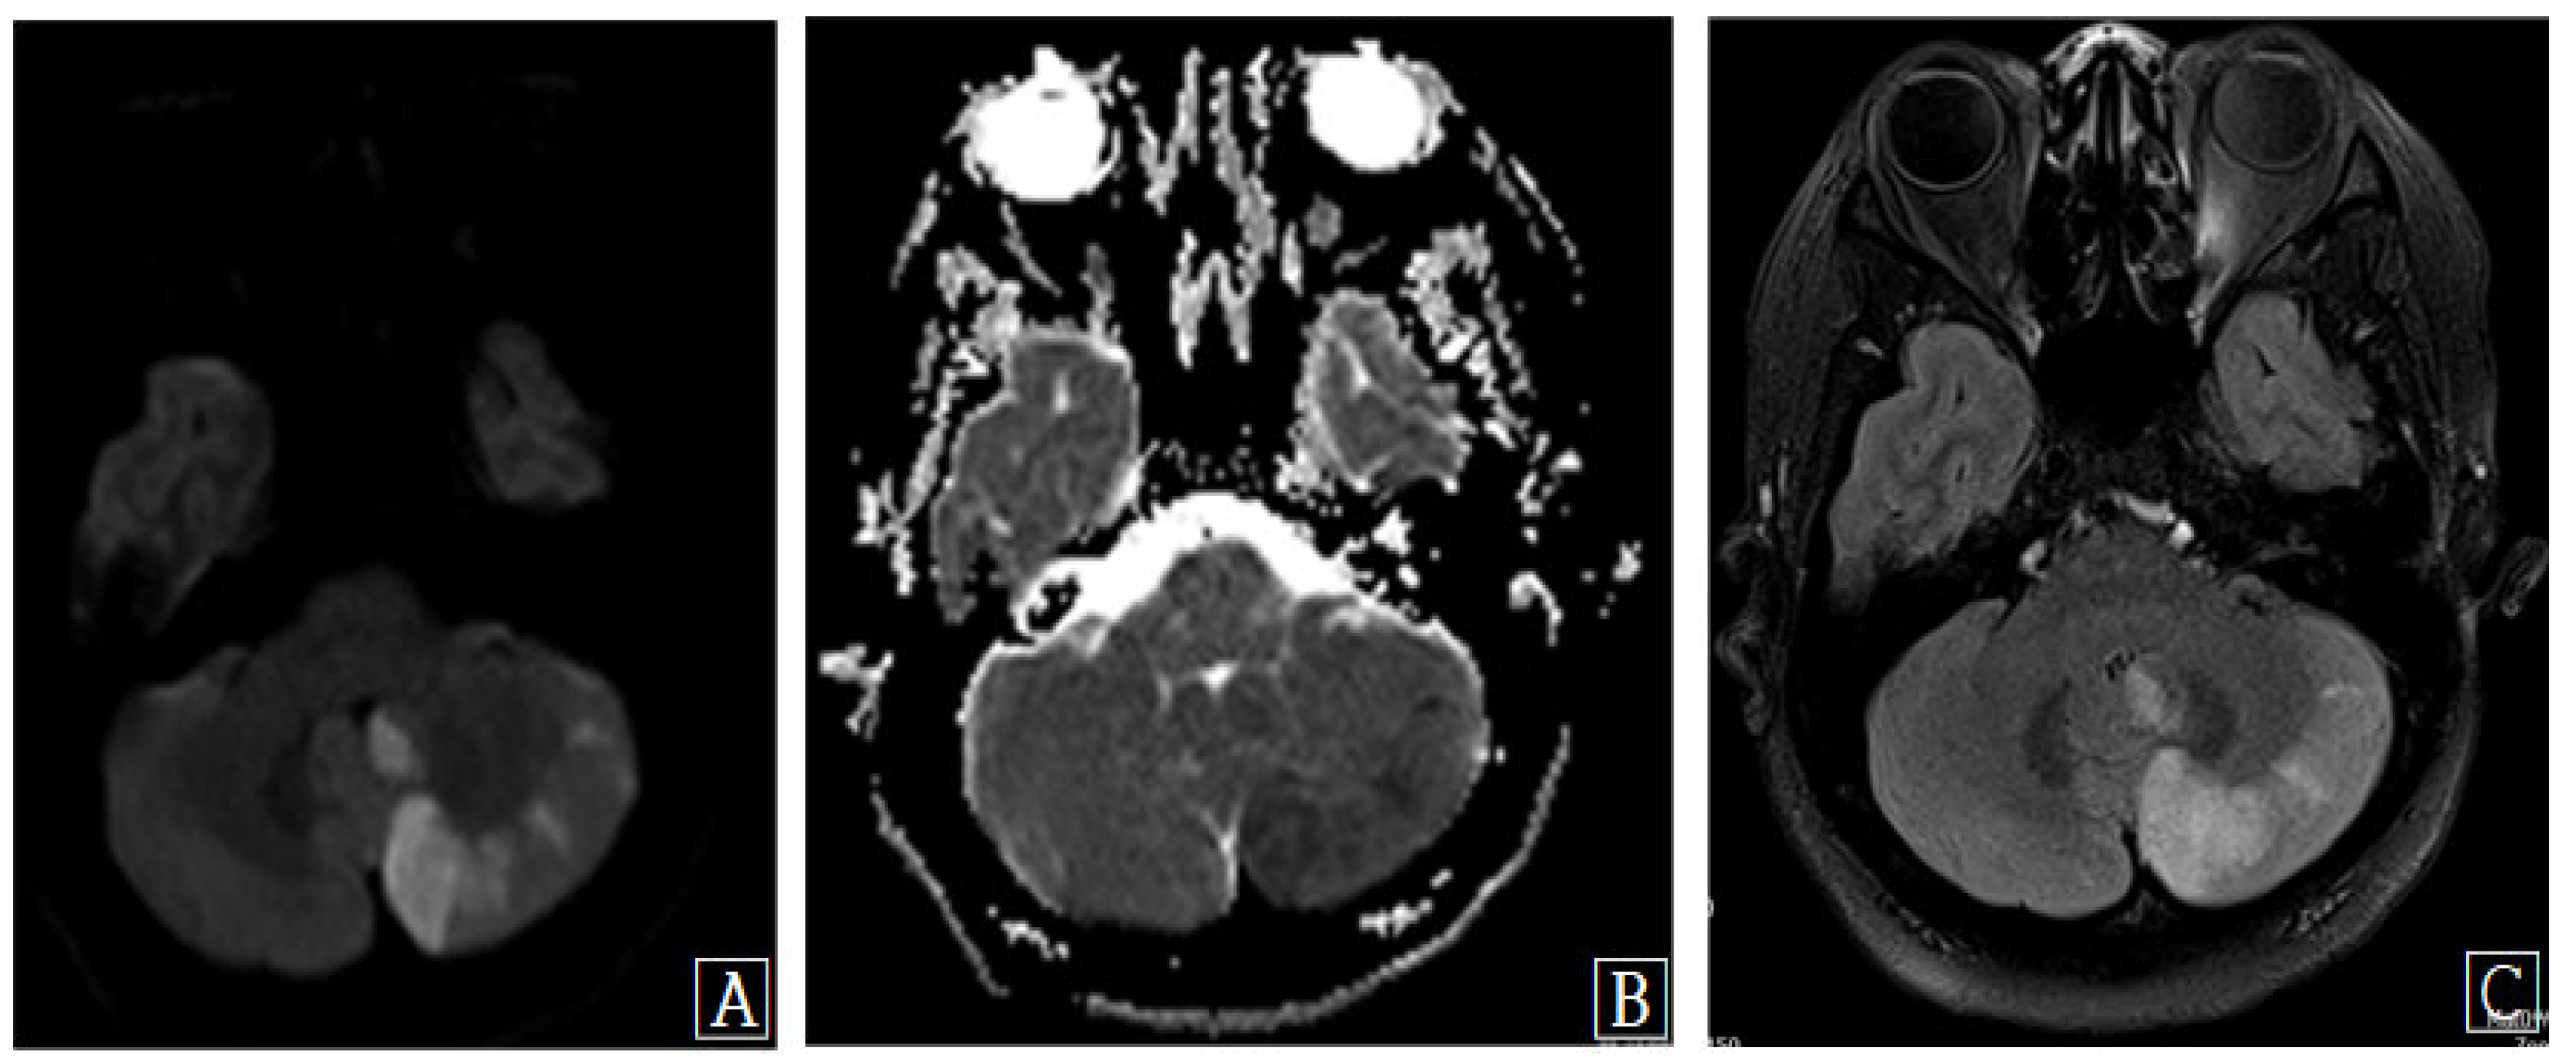

Vertebral artery dissection (VAD) is a rare vascular cause of acute stroke. Although VAD may be classified as spontaneous or traumatic, it is increasingly recognized that trivial mechanical stress typically precipitates this potentially dangerous condition. Herein, we report a rare case of VAD and acute stroke following anterior cervical decompression and artificial disc replacement (ADR). To our knowledge, there have been no other cases of acute vertebrobasilar stroke caused by VAD following anterior cervical decompression and ADR. This case highlights that, although rare, acute vertebrobasilar stroke may occur after the anterior cervical approach.